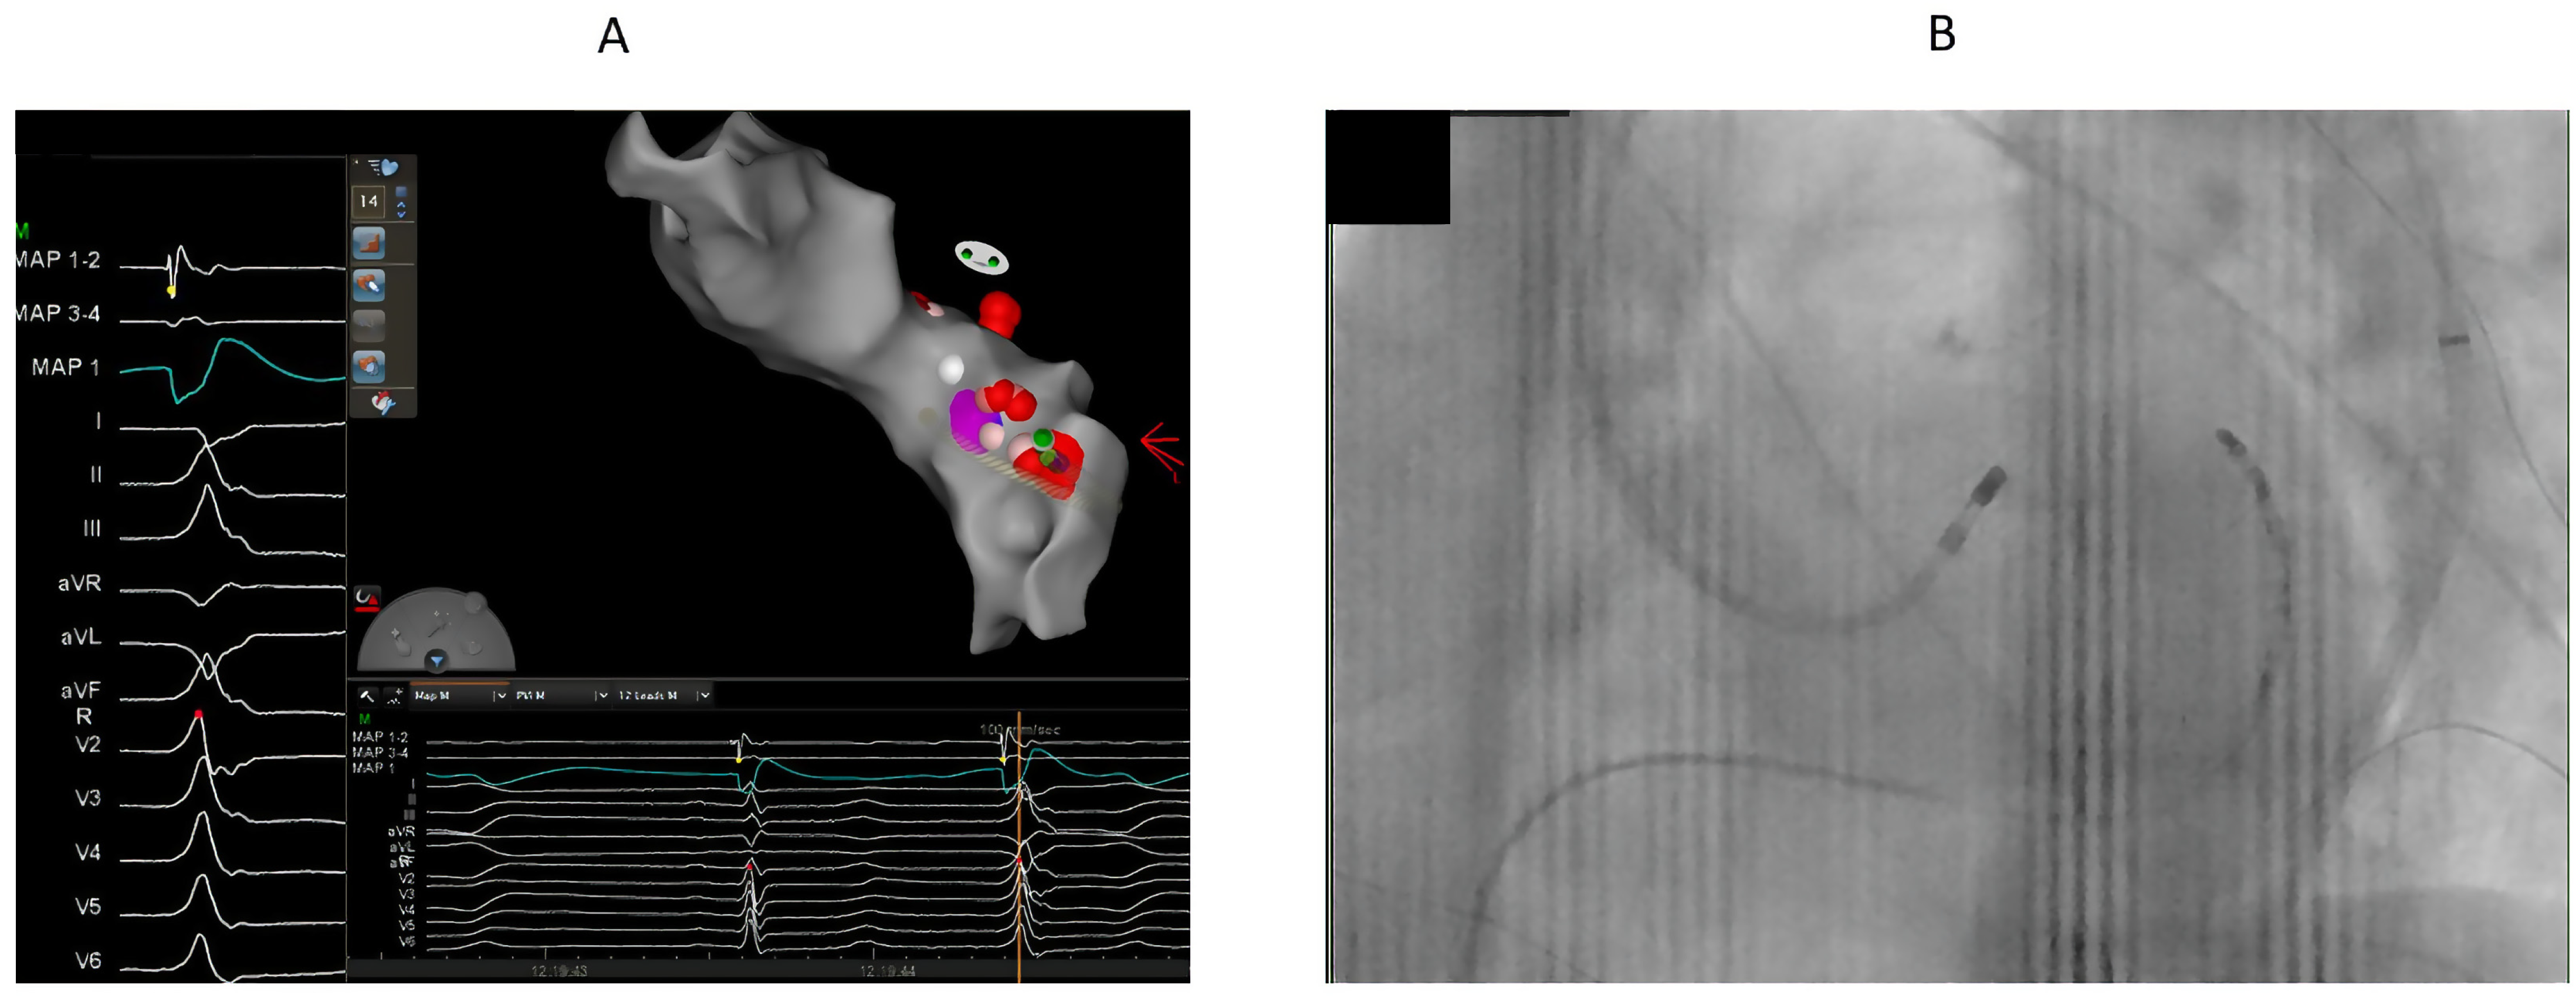

7.1. Procedure

8.2. Ablation Sites